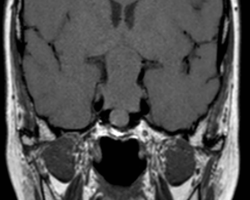

Un homme de 55 ans, n’ayant aucun antécédent personnel est envoyé pour réaliser une IRM par son ORL pour exploration d’acouphènes associés à une hypoacousie droite ainsi que des vertiges et une paralysie faciale périphérique droite d’apparition récente. […]